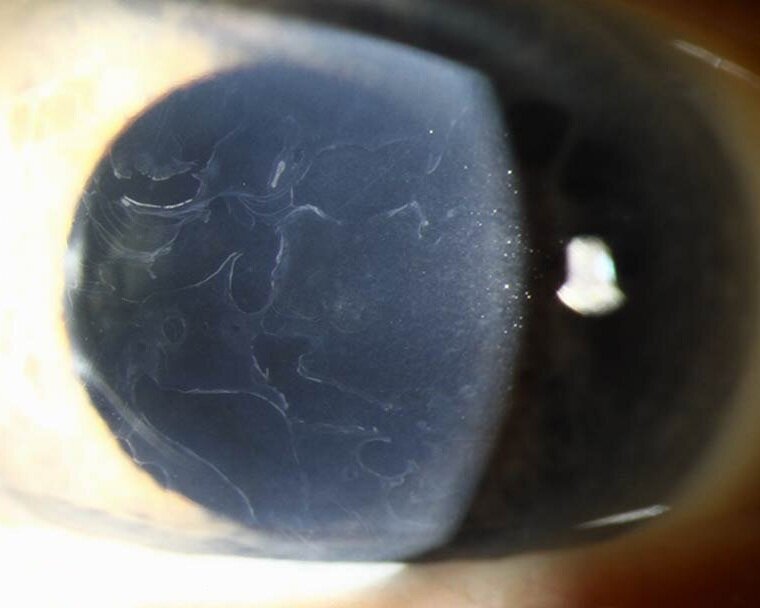

@drgunjand Map dot fingerprint dystrophy with recurrent corneal abrasions